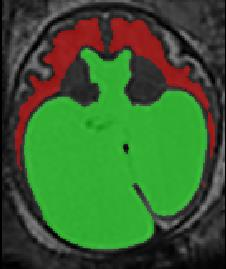

Limiting failures of machine learning systems is of paramount importance for safety-critical applications. In order to improve the robustness of machine learning systems, Distributionally Robust Optimization (DRO) has been proposed as a generalization of Empirical Risk Minimization (ERM). However, its use in deep learning has been severely restricted due to the relative inefficiency of the optimizers available for DRO in comparison to the wide-spread variants of Stochastic Gradient Descent (SGD) optimizers for ERM. We propose SGD with hardness weighted sampling, a principled and efficient optimization method for DRO in machine learning that is particularly suited in the context of deep learning. Similar to a hard example mining strategy in practice, the proposed algorithm is straightforward to implement and computationally as efficient as SGD-based optimizers used for deep learning, requiring minimal overhead computation. In contrast to typical ad hoc hard mining approaches, we prove the convergence of our DRO algorithm for over-parameterized deep learning networks with ReLU activation and a finite number of layers and parameters. Our experiments on fetal brain 3D MRI segmentation and brain tumor segmentation in MRI demonstrate the feasibility and the usefulness of our approach. Using our hardness weighted sampling for training a state-of-the-art deep learning pipeline leads to improved robustness to anatomical variabilities in automatic fetal brain 3D MRI segmentation using deep learning and to improved robustness to the image protocol variations in brain tumor segmentation. Our code is available at https://github.com/LucasFidon/HardnessWeightedSampler.